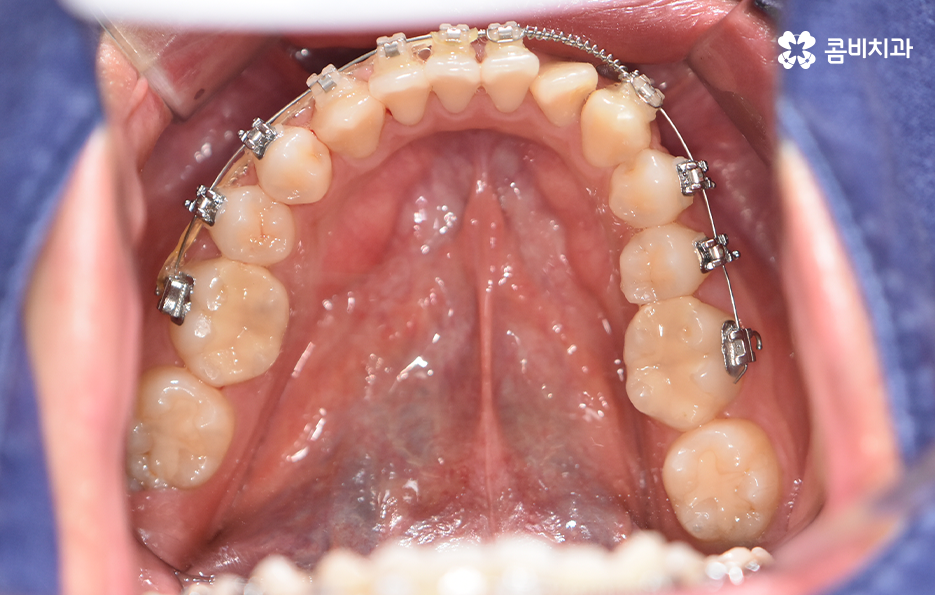

오늘 포스팅에서 보여지는 사진에서는 비발치 교정으로 덧니 교정이 가능했던 사례입니다. 덧니 교정 사례에서 발치교정 케이스는 흔한 치료 방법이긴 하지만 발치에 대한 판단은 치열만이 아니라 골격과 얼굴형을 종합적으로 고려하여 판단하고 치아를 얼마나 이동시켜야 할지 예측하여 판단하기 때문에 3D CT 등의 첨단 장비를 통한 검진과 경험 많은 교정 전문의와 충분히 상의하고 결정해야 합니다

종합하면 발치교정의 필요성은 얼굴과의 조화, 골격 그리고 교합 등을 전체적으로 고려하여 판단하기 때문에 각 환자분들이 필요한 치아의 이동 정도를 정확히 예측하고 필요한 치아 이동 공간을 확보함에 있어서 발치교정이 적합할지 아니면 비발치적인 방법으로도 치아 이동 공간이 확보 가능한지 따져보고 있으며 발치교정이 아니더라도 치간삭제, 악궁확장, 어금니 후방이동과 같은 방법으로 공간 확보가 가능하기 때문에 각 환자분들에게 적합한 1:1 맞춤형 치료가 진행되고 있어요